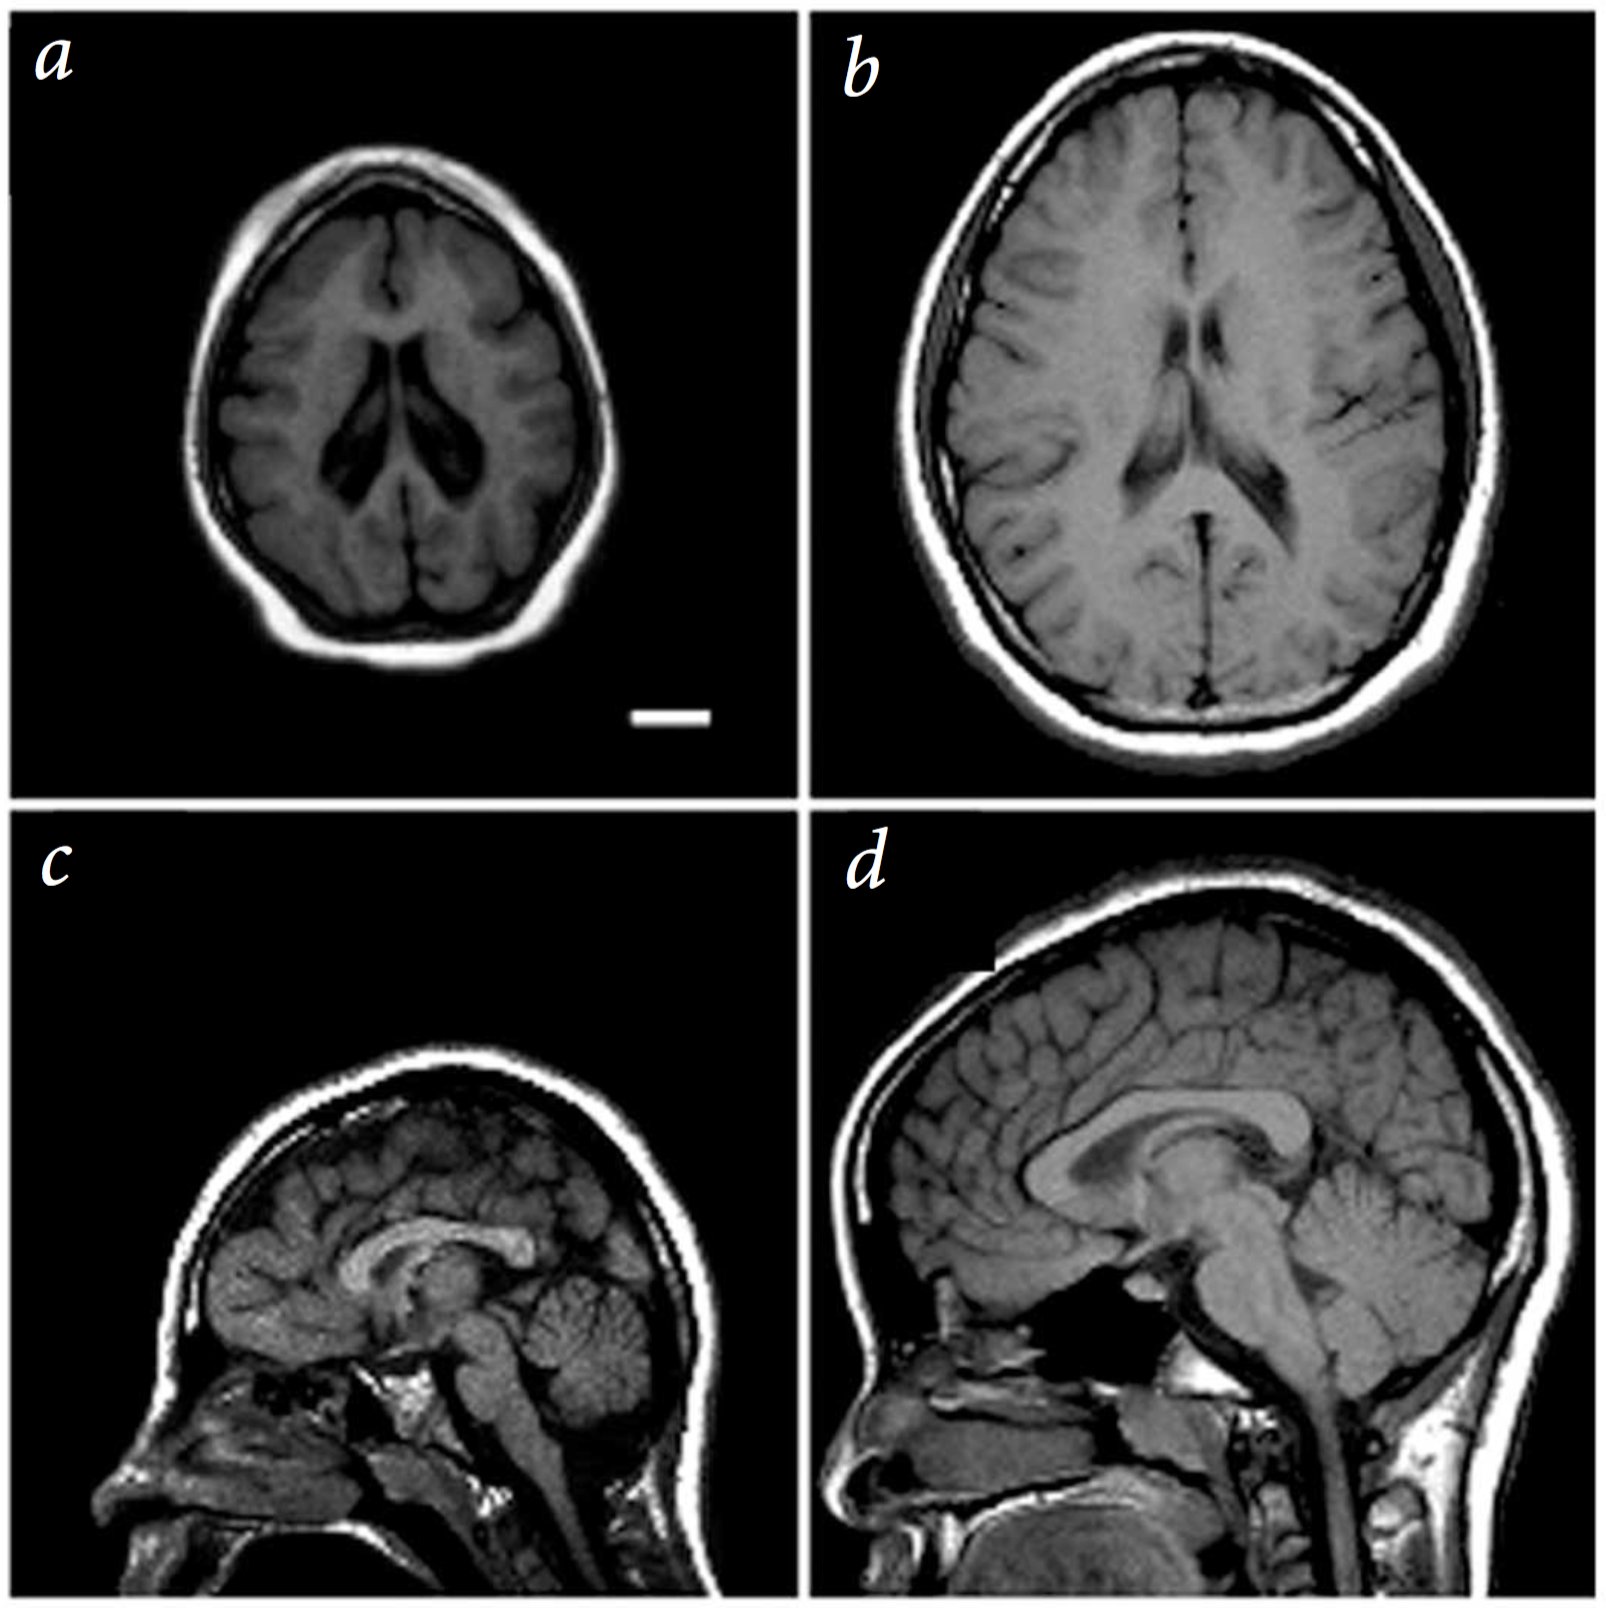

A single mutation can lead to dramatic brain size defects

Mutation in a spindle pole gene call ASPM1 (altered mitosis during brain development)

Bond:2002, see also Neuroscience 5e Fig. 1.1

Now mutations in single genes in the right place in our genome can cause drastic effects on the formation of our brains wiring.

For example, shown here is a person with a mutation in ASPM1 a protein used to make spindle poles for mitotic stem cells during embryonic development.

But most single gene mutations do not cause such drastic effects, with a more subtle and complex set of genetic and environmental risk factors causing neurological disease, similar to and probably exceeding the complex etiology of cancer.

2cm scale bar. left 13yr old female patient. right 11 yr old control.